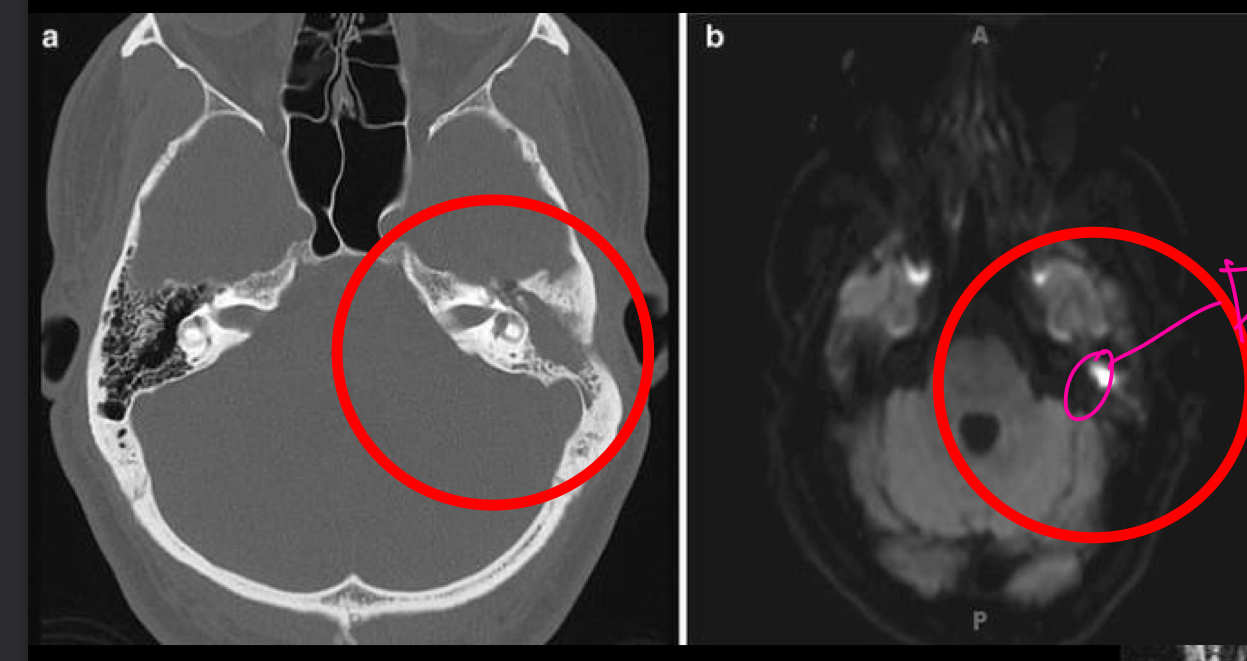

**TC Mejor estudio **

Otitis media

Masa bien definida en oido medio que tapa aire

RM DE OTITIS MEDIA

indicada en complicaciones

T1= masa hipointesa

t2= hiperintensa